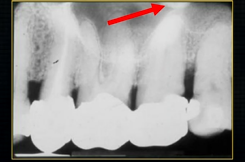

the upper jaw - the maxilla - what is circled in red?

the nasal cavity

what is seen here?

the nasal septum and the inferior nasal concha

what is the bottom arrow showing?

the floor of the nose - just above the apices of the upper anterior teeth